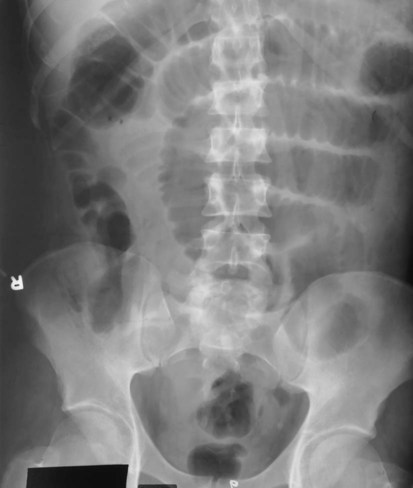

The plain abdominal radiograph (KUB) shown in Fig. 13-20 is from a healthy, ambulatory adult. The many meters of small intestine are generally not visible in the central portion of the abdomen. In the average ambulatory adult, a large collection of gas in the small intestine is considered abnormal. With no gas present, the small bowel simply blends in with other soft tissue structures. Therefore, radiographic examination of the alimentary canal requires the introduction of contrast media for visualization.

The radiographic procedure designed to study the large intestine is most commonly termed a barium enema. Alternative designations include BE, BaE, and lower GI series. Fig. 13-3 shows a large bowel or colon filled with a combination of air and barium, referred to as a double-contrast barium enema. Note: This patient has situs inversus, in which abdominal and thoracic organs are reversed from their normal orientation within the body.